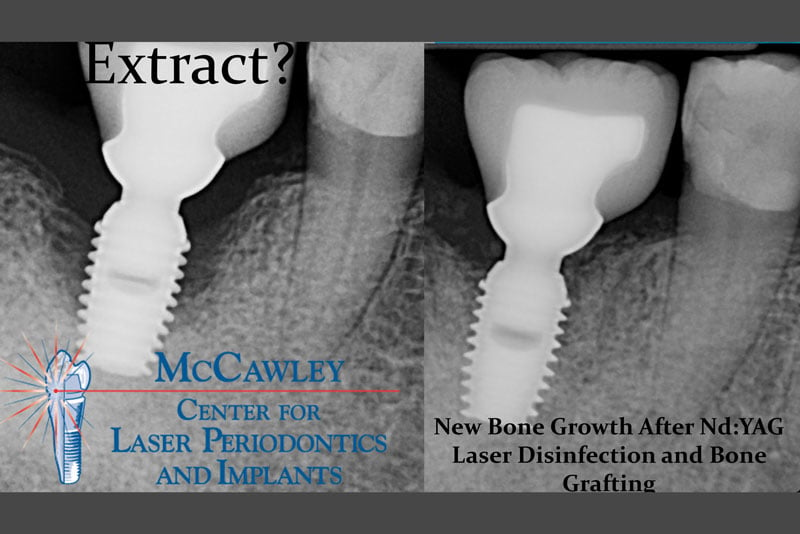

Our office has been at the forefront of dental technology since 1990, pioneering laser periodontal therapy and treating over 5000 patients with it. The Nd:YAG

Drs. Tom and Mark McCawley of Fort Lauderdale, FL are helping many patients restore their smile with dental implants which have been lost to periodontal